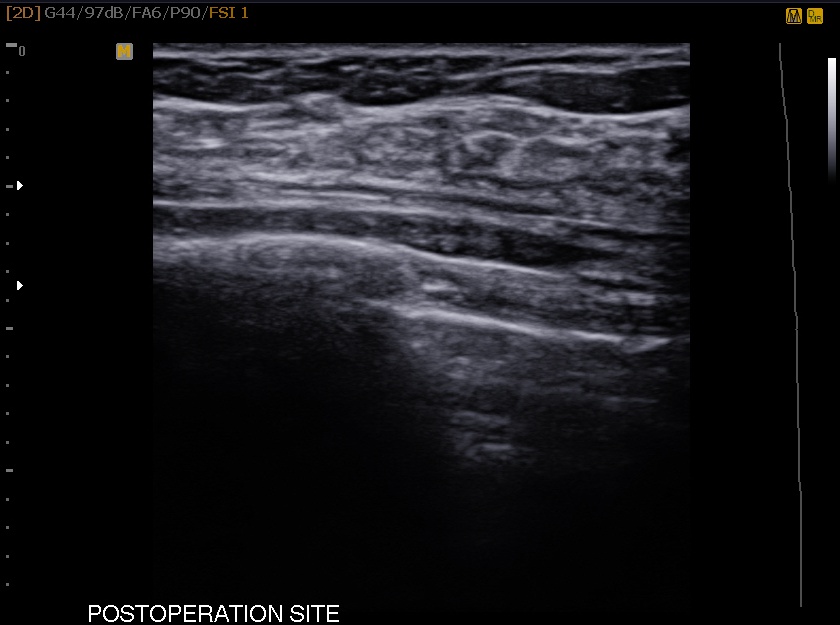

¸¾¸ðÅè½Ã¼ú»ç·Ê 28¼¼ ¿©¼ºÀ¸·Î ÁÂÃø À¯¹æ¿¡ ¸¸Á®Áö´Â ȤÀ¸·Î ³»¿øÇÏ¿© Á¶Á÷°Ë»ç ½ÃÇàÇÏ¿´°í Á¶Á÷°Ë»ç °á°ú fibroadenoma Áø´ÜµÇ¾úÀ¸¸ç ȯÀÚ ¿øÇϼż ¸¾¸ðÅè ¼ö¼ú ½ÃÇàÇÏ¿´½À´Ï´Ù.